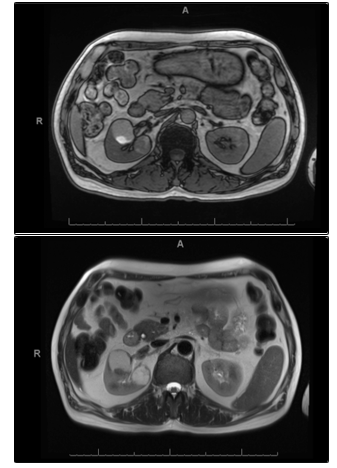

Magnetic Resonance Imaging (MRI) was carried out to investigate the aetiology of the observed cysts (Fig 2). Cyst images reviewed by the urology and radiology MDT and the conclusion was that the cysts were of a Bosniak IIF grade with no current evidence of malignancy. The MDT recommended follow up of the renal cysts after 6 months and every year thereafter. Given the risk of malignancy-risk associated with Bosniak IIF grading, rituximab was commenced over cyclophosphamide.

Fig (2): MRI both kidneys T1 signal (Top) and T2 signal (Bottom). The more anterior cyst contains an area of T1 high signal posteriorly which does not enhance appreciably and would be consistent with proteinaceous/haemorrhagic debris. The more posterior lesion demonstrates multiple septations.